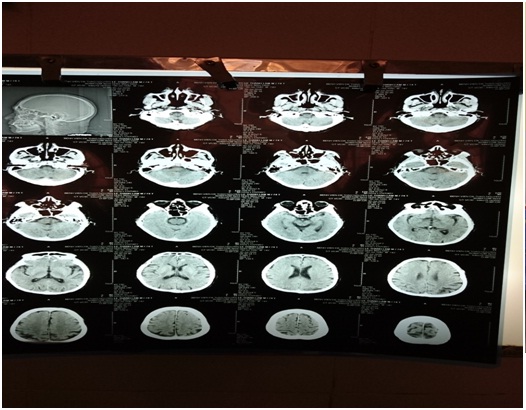

Hình ảnh chụp cắt lớp CT bệnh nhân

Bệnh nhân nam 74 tuổi ,vào viện lúc 6h00 ngày 29/7 năm 2016. Lí do : yếu ½ người phải+ nói ngọng. Theo người nhà kể lại: từ 4h30 phút cùng ngày, bệnh nhân ngủ dậy, sau khi đánh răng thì đột ngột xuất hiện nói khó, yếu ½ người phải, tình trạng liệt ngày 1 tăng, được gia đình phát hiện và đưa vào viện. Tình trạng lúc vào bệnh nhân tỉnh, thất ngôn, liệt mặt trung ương phải, Mạch : 80l/P. HA: 160/80 mmHg, yếu ½ người phải, cơ lực tay phải 3/5, chân phải 3/5, giảm cảm giác nửa người phải, 6 điểm NIHSS, bệnh nhân được chụp CT Scaner: không thấy hình ảnh bất thường. Bệnh nhân được chẩn đoán: đột quỵ não giờ thứ 2.